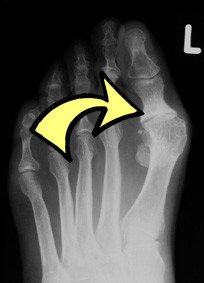

Rechts bzw. unten sieht man Röntgenaufnahmen des Kunstgelenkes nur 3 Jahre nach der Implantation.

Es finden sich Lockerungszeichen an der Basis des Grundgliedes der Grosszehe, ausserdem ausgeprägte zystische Veränderungen (Osteolysen) im Bereich des ersten Mittelfussknochens.